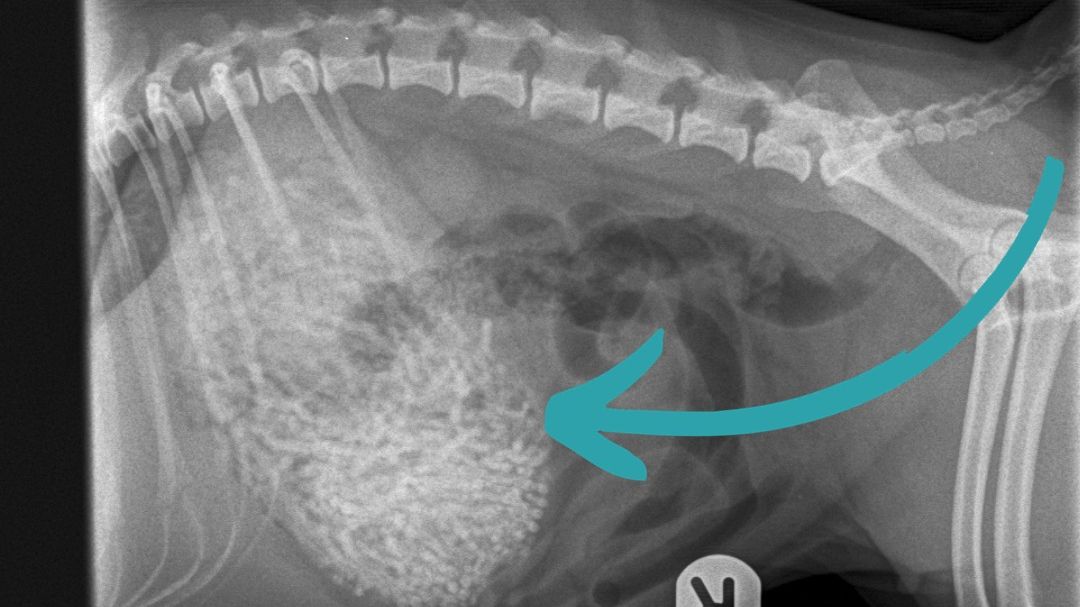

Prvi pregled u veterinarskoj ordinaciji pokazao je da pas ima nešto neobično u stomaku, pa su se odmah odlučili na operaciju.

Veterinarka Emili Vitbi (Emily Whitby) rekla je da su uklonili 50 do 60 gumica teških 200 grama – Ham je teška samo šest kilograma.